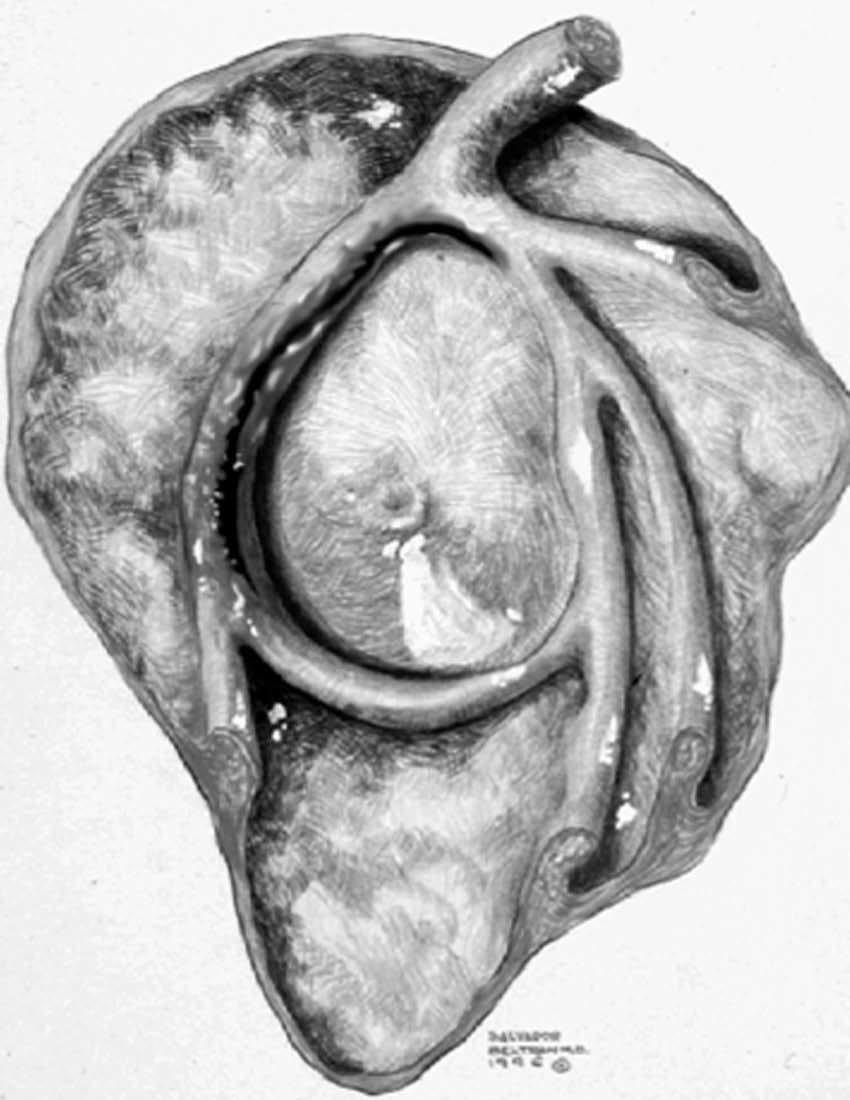

ALPSA (anterior labroliamentous periosteal avulsion)

Al igual que en el apartado anterior, existe también una separación de LG junto con la cápsula y el periostio, pero a diferencia de las lesiones de Bankart o Perthes, el LG se desplaza hacia dentro, por detrás del borde de la glenoides18 (fig. 12). La lesión de ALPSA puede cicatrizar por sinovialización (fig. 12), pero continúa siendo de carácter inestable.

Fig. 12.--ALPSA (anterior labroliamentous periosteal avulsion) agudo (A) y crónico (B). Nótese la separación del labio glenoideo y su desplazamiento posterior y medial por detrás del reborde glenoideo (flecha en A). En una fase crónica el labio glenoideo no se distingue como una estructura separada, sino como un engrosamiento de la unión entre el labio, la cápsula y el periostio (flecha en B).